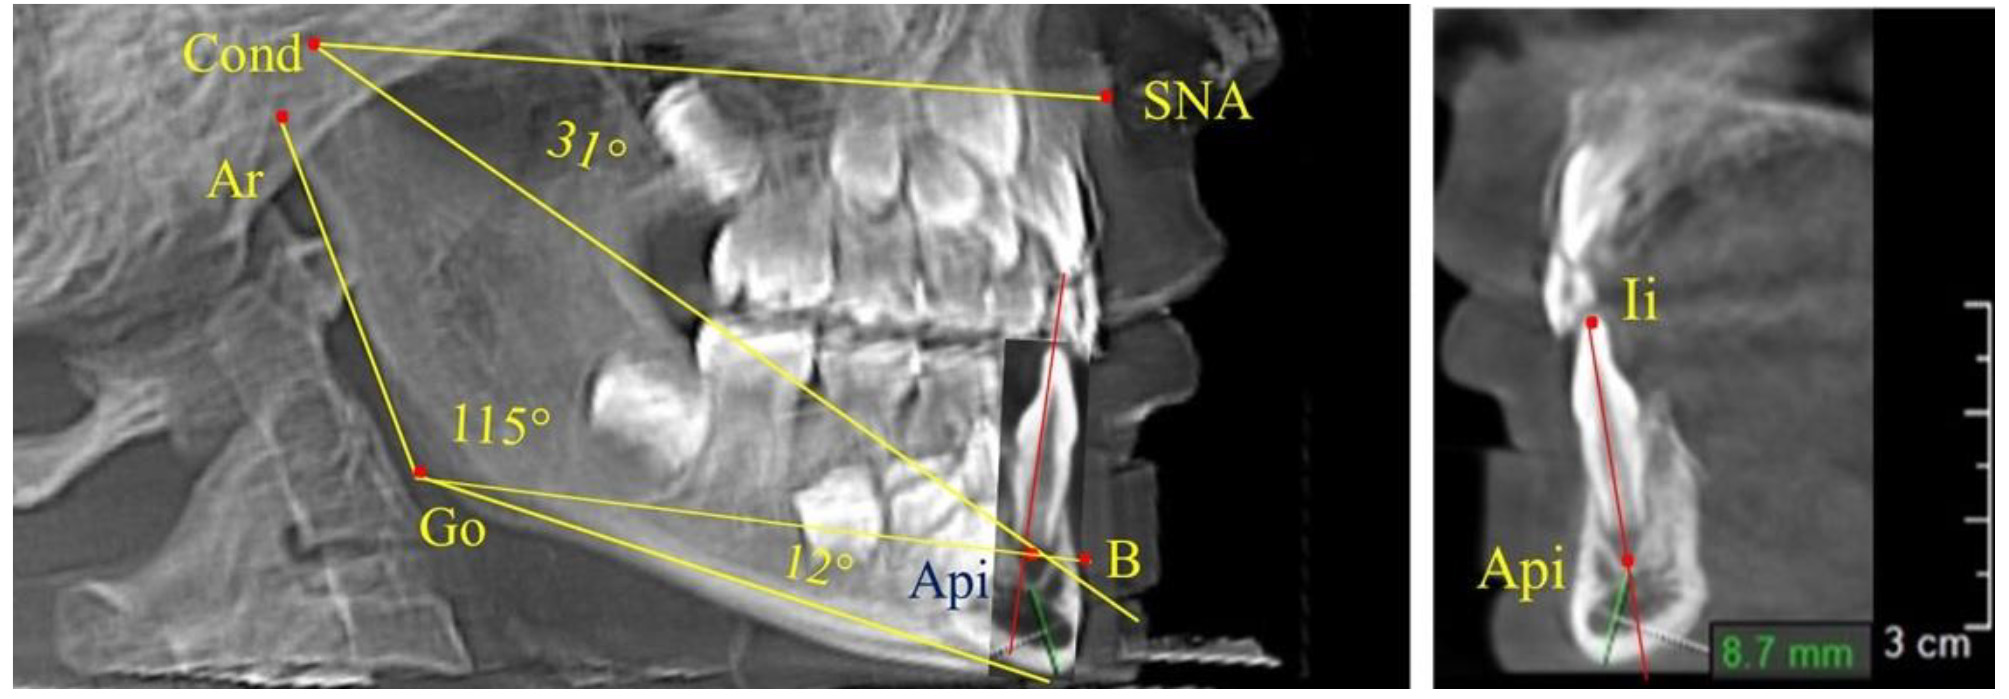

После смены всех молочных зубов (анализ 9 ТРГ) и после прорезывания вторых постоянных моляров (7 человек) происходил очередной этап подъема высоты прикуса с увеличением размеров костей гнатической части лица. Однако величина основного угла гнатической части лица SNA-Cond-Api, так же как в молочном и сменном прикусе, в норме составляла (30,02 ± 1,25)°, что не имело достоверных различий (р ˃ 0,05) с аналогичным параметром, анализируемом в других группах исследования. Угол нижней челюсти и его составляющие отличались вариабельностью параметров при различных показателях нижнечелюстного угла (рис. 6).

Рис. 6. Варианты 3D рентгенограмм детей после смены всех молочных зубов (а) и после прорезывания вторых моляров (б)

Таким образом, данные, полученные при исследовании детей с физиологическим прикусом в различные периоды онтогенеза, показали, что величина основного угла гнатической части лица SNA-Cond-Api была относительно стабильным параметром, вне зависимости от линейных параметров челюстных костей. Данный показатель может служить ориентиром для дифференциальной диагностики зубоальвеолярных и гнатических форм аномалий окклюзии в вертикальном направлении.

При анализе 16 рентгенограмм с аномалиями окклюзии в вертикальном направлении были выявлены признаки изменения основного гнатического угла. Так, для гнатических аномалий глубокой резцовой окклюзии/дизокклюзии (9 человек) отмечалось уменьшение угла гнатической части лица, величина которого была менее 26°. В то же время для гнатических аномалий (7 человек) вертикальной резцовой дизокклюзии («открытый» прикус) определялось увеличение угла гнатической части лица, который превышал значения в 33° (рис. 7).

Рис. 7. Варианты ТРГ при глубоком прикусе (а) и при открытом прикусе (б)

На представленных клинических примерах, несмотря на различия параметров основного угла гнатической части лица, определялись однотипные варианты угла нижней челюсти Ar-Go-Me и его составных частей Ar-Go-Api и Api-Go-Me.